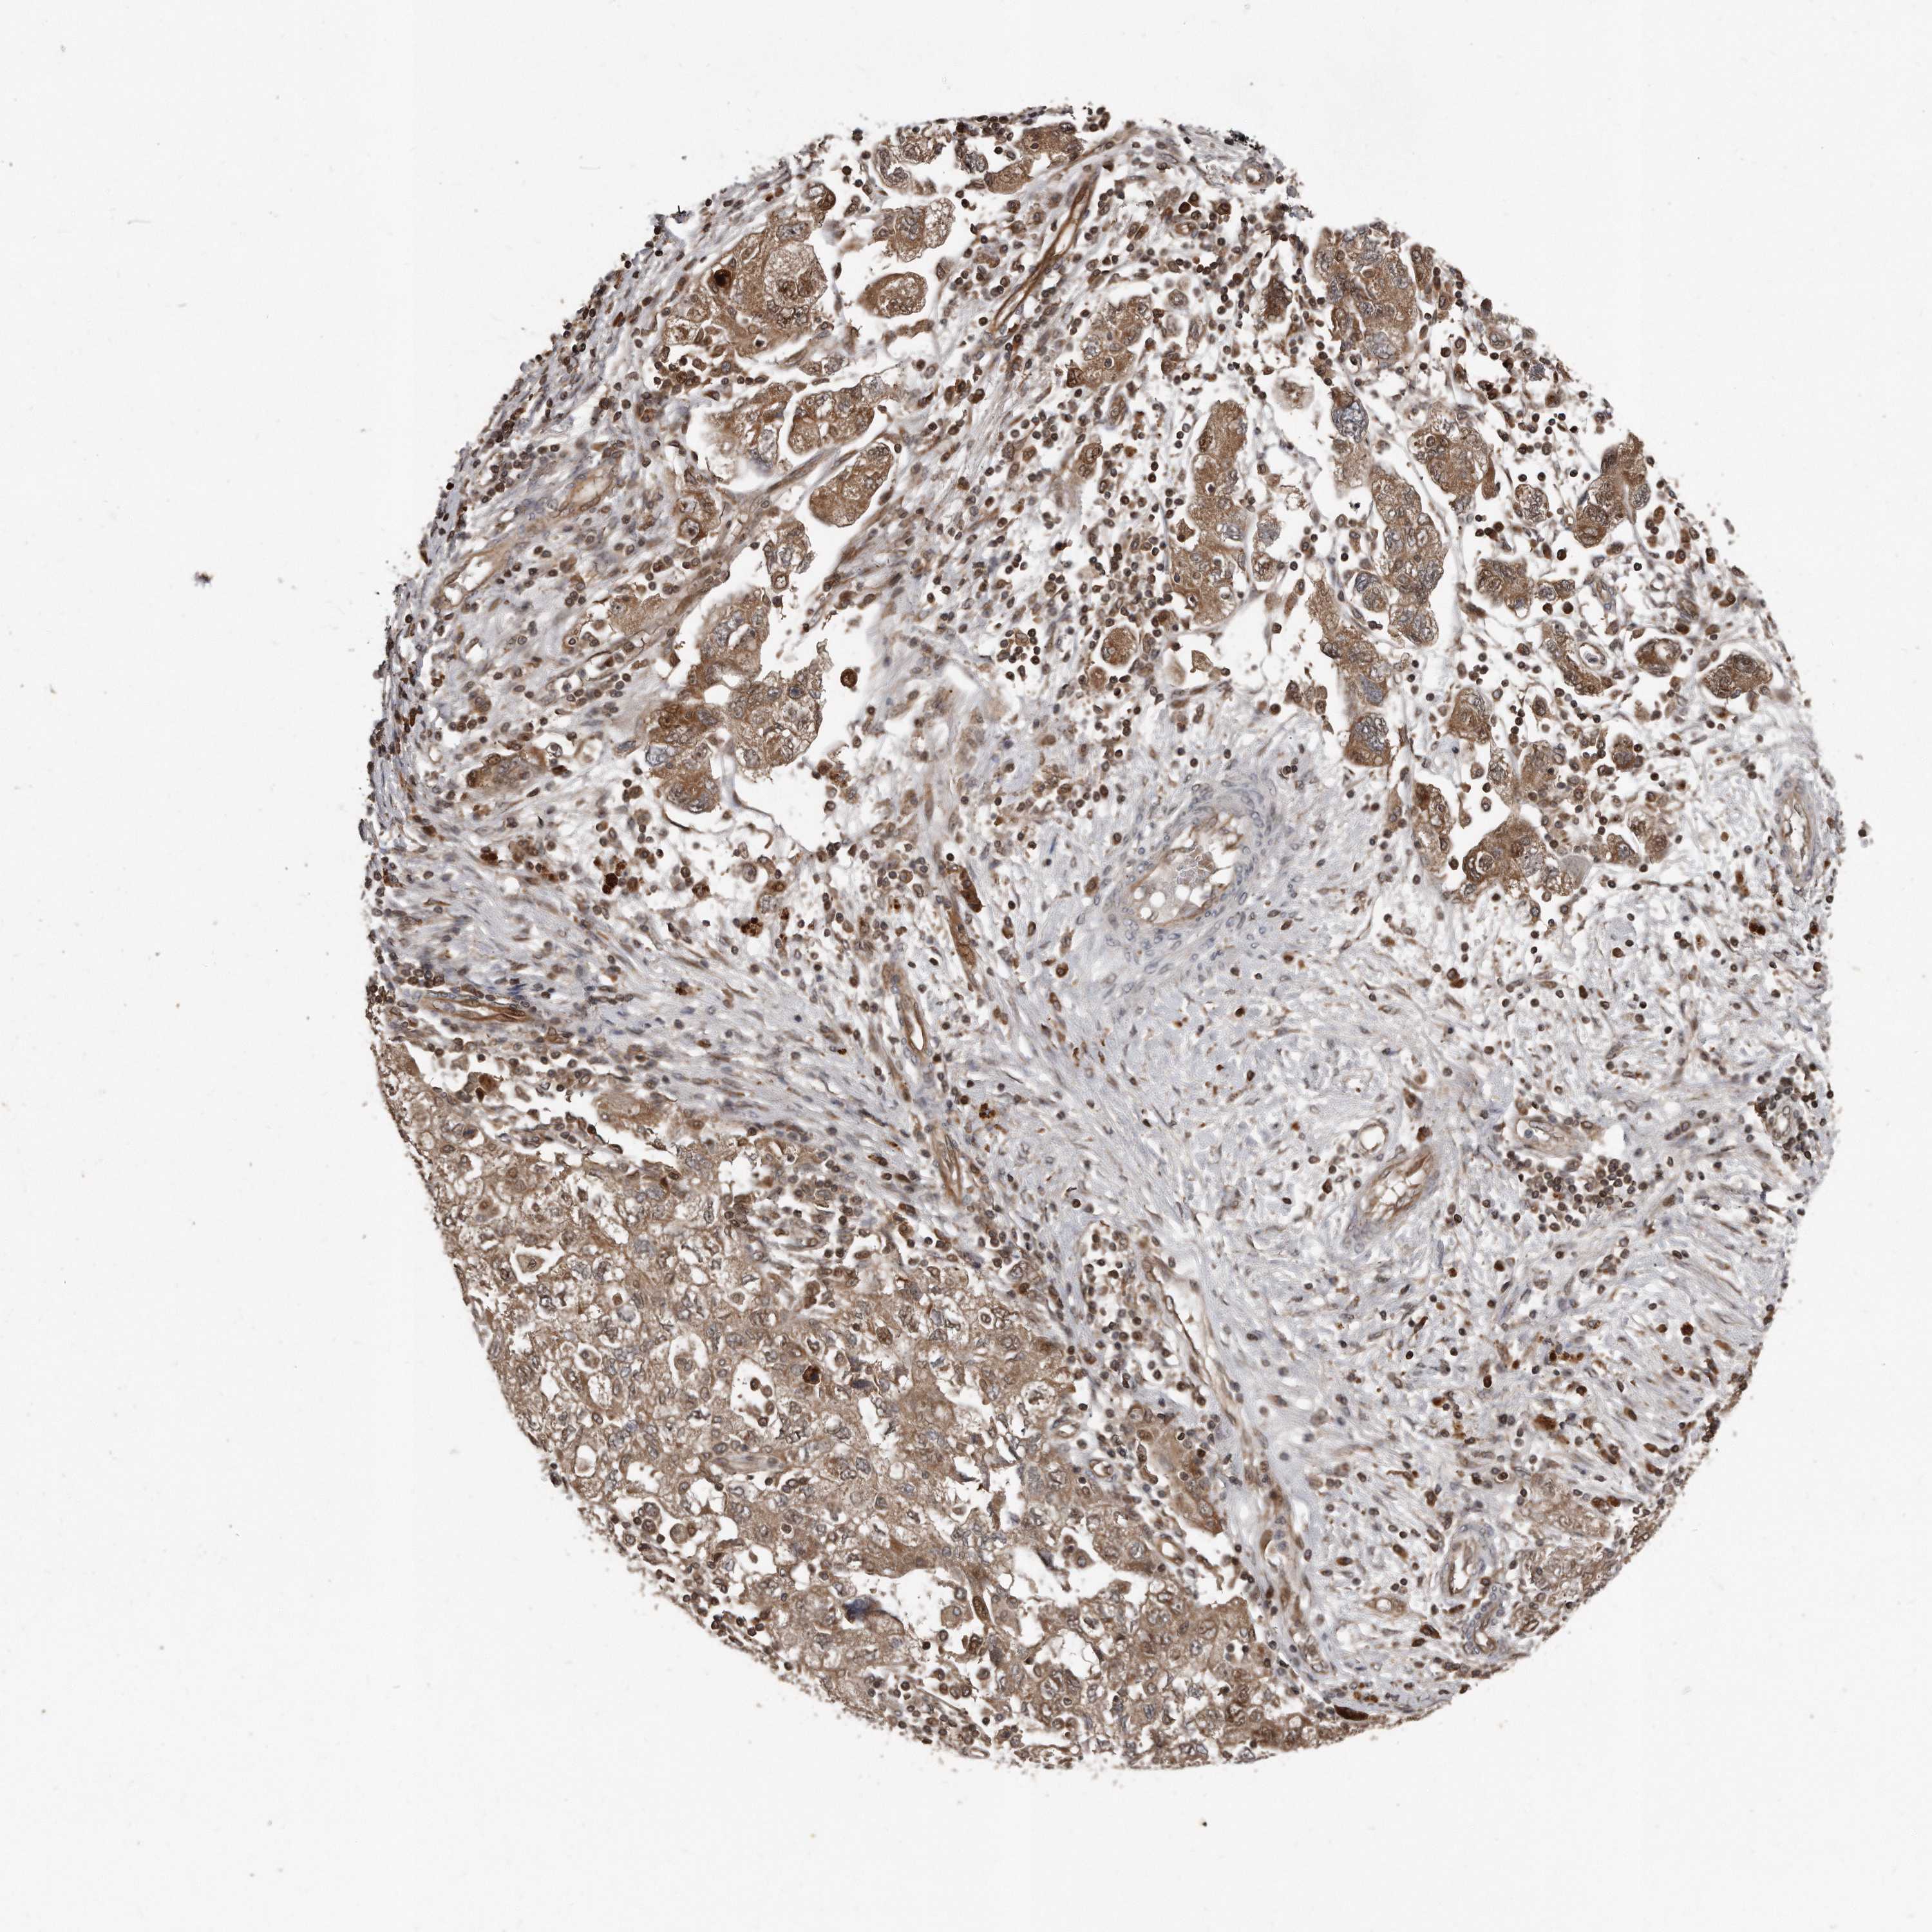

OVARIAN CANCER - Protein expressioni

A mouse-over function shows sample information and annotation data. Click on an image to view it in a full screen mode. Samples can be filtered based on level of antibody staining by selecting one or several of the following categories: high, medium, low and not detected. The assay and annotation is described here.

Note that samples used for immunohistochemistry by the Human Protein Atlas do not correspond to samples in the TCGA dataset.

Antibody stainingi

Antibody staining in the annotated cell types in the current human tissue is reported as not detected, low, medium, or high, based on conventional immunohistochemistry profiling in selected tissues. This score is based on the combination of the staining intensity and fraction of stained cells.

Each image is clickable and will lead to virtual microscopy that enables deeper exploration of all samples and also displays staining intensity scores, fraction scores and subcellular localization as well as patient and tissue information for each sample.

Antibody HPA028612

Staining

High

Medium

Low

Not detected

Intensity

Strong

Moderate

Weak

Negative

Quantity

>75%

75%-25%

<25%

None

Location

Nuclear

Cytoplasmic/membranous

Cytoplasmic/membranous,nuclear

Cystadenocarcinoma, serous, NOS

Carcinoma, endometroid

Cystadenocarcinoma, mucinous, NOS

Carcinoma, NOS